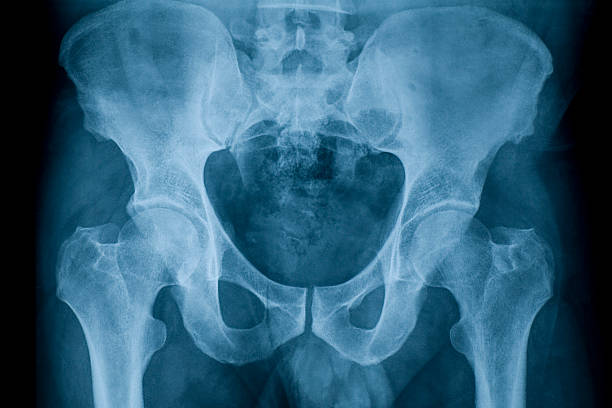

관절염

엉덩이 관절의 염증이나 변형으로 인해 엉덩이 통증이 발생할 수 있습니다. 나이가 들어가면서 관절염이 악화되어 엉덩이 통증이 생기는 경우가 많습니다. 이러한 경우에는 전문의의 치료와 적절한 관리가 필요합니다.